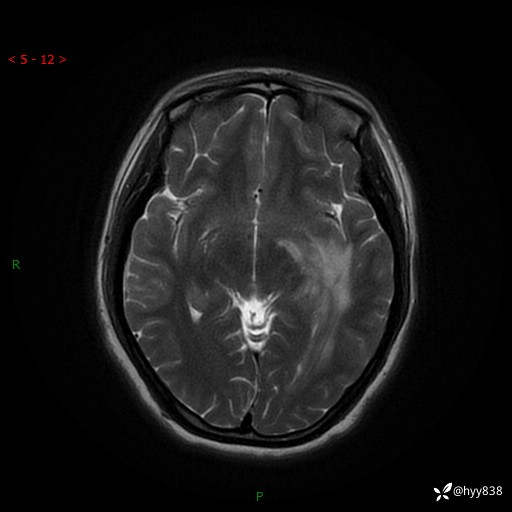

颅脑MRI平扫+增强